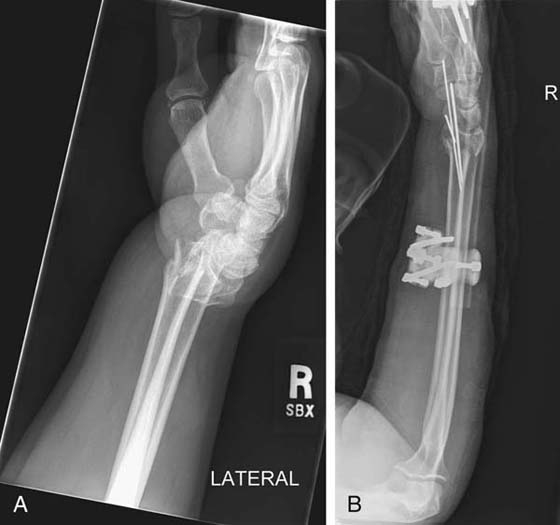

Bridging (e.g., across the radiocarpal articulation) or nonbridging external fixation devices41 (Figs. 70-25 and 70-26) are sometimes the treatment of choice for high-energy impact injuries. The therapist must take the extent of soft-tissue injury into account when planning therapy. When a DRF is treated with external fixation, the complications most commonly seen are pin-site infection, edema, first webspace tightness, and intrinsic tightness of the digits. If a patient is referred to hand therapy with the external fixation device still in place, examination should include the following: ROM of shoulder, elbow, and digits and edema measurement using a tape measure. Treatment is the same as with casting: retrograde massage, use of self-adherent elasticized wrap, and active ROM. Pin-site care should also be reviewed with the patient. The patient should be instructed to keep the pin sites dry and clean at all times because the pin is a conduit of infection.42 Daily cleaning using saline solution or diluted hydrogen peroxide applied with a clean cotton-tipped applicator is recommended by some, but newer evidence suggests that this may not be necessary.42 Tendon-gliding exercises performed on an hourly basis should also be emphasized. Special attention should be placed on the index finger because the dorsal pins are usually in close proximity to the extensor indicis proprius and extensor digitorum communis. Another problem seen is dorsal radial sensory nerve involvement, most typically caused by placement of the proximal pin site too close to this nerve. This can lead to CRPS; therefore, a sensory examination should also include the dorsoradial aspect of the hand. Acute carpal tunnel syndrome can also be experienced in this population, due to trauma caused by the injury and/or the position of the wrist in the fixation device. The surgeon should be contacted immediately by the patient or hand therapist if he or she experiences any sensory changes.

images

Figure 70-25 A, Radiograph of distal radius fracture. B, Radiograph of external fixation device with percutaneous pinning for a distal radius fracture. (Courtesy of Daniel DiCristino, MD, Fayetteville, New York.)